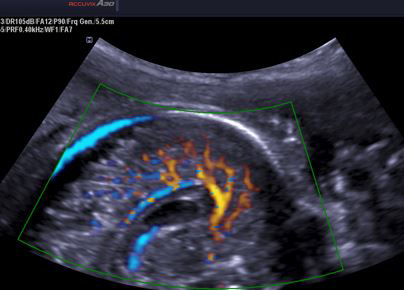

Ecografía en reproducción

La ecografía se ha convertido en la actualidad en la herramienta diagnóstica básica del ginecólogo, en todas y cada una de las subespecialidades que abarca. En el campo de la medicina reproductiva ha desplazado en muchos casos a otras pruebas más complejas o...